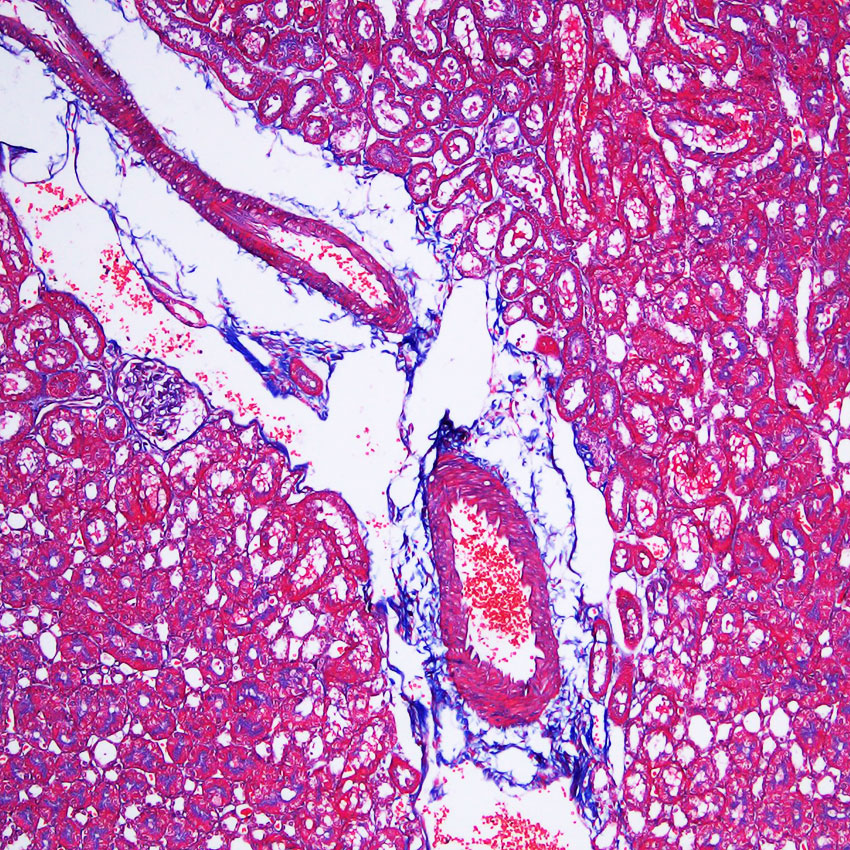

结缔组织狭义上是指其含有的三种纤维:胶原纤维、网状纤维、弹力纤维。而胶原纤维是分布最广、含量最多的一种纤维。Masson 三色染色又称马松染色,是结缔组织染色中最经典的一种方法,是胶原纤维染色权威而经典的技术方法。所谓三色染色通常是指染胞核和能选择性的显示胶原纤维和肌纤维。该法染色原理与阴离子染料分子的大小和组织的渗透有关:分子的大小由分子量来体现,小分子量易穿透结构致密、渗透性低的组织,而大分子量则只能进入结构疏松的、渗透性高的组织。然而,淡绿或苯胺蓝染料的分子量很大,因此 Masson 染色后肌纤维呈红色,胶原纤维呈绿色或蓝色,主要用于区分胶原纤维和肌纤维。

细胞核红褐色到棕褐色

胶原纤维、弹力纤维蓝色

肌肉纤维、红细胞红色

细胞浆及其他组织背景紫红色到红色